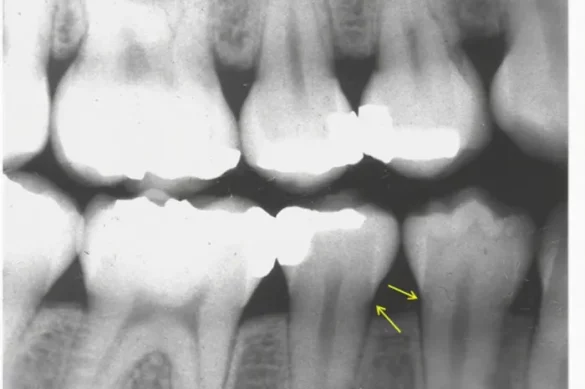

Radiographs (dental X-rays) are the maximum correct and dependable technique to assess alveolar bone levels. On an X-ray, the wholesome alveolar crest seems as a radiopaque (white) line simply beneathneath the gum margin, following the contour of the 2 adjoining tooth.

Standard periapical or bitewing radiographs offer a clean view of the connection among the alveolar crest and the CEJ. The maximum normally used approach includes measuring the space among those landmarks.

A wholesome alveolar bone stage refers to the location of the bone with regards to the cementoenamel junction (CEJ) of a enamel, that is wherein the tooth masking the crown meets the cementum of the root. Generally, the pinnacle of the alveolar crest lies among zero.five to 2.zero millimeters underneath the CEJ in a wholesome adult.